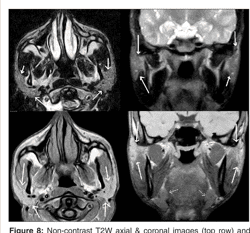

Parotid gland radiographics image This image shows Parotid gland radiographics.